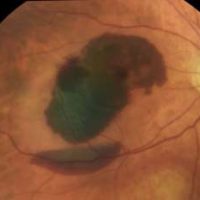

Choroidal Nevus

A choroidal nevus (plural: nevi) is typically a darkly pigmented lesion found in the back of the eye. It is similar to a freckle or mole found on the skin and arises from the pigment-containing cells in the choroid, the layer of the eye just under the white outer wall (sclera). (Figures 1 and 2).

SYMPTOMS

Most commonly, a choroidal nevus does not cause any symptoms and is found on routine eye exam. However, sometimes nevi under the center of the retina (the macula) can cause blurred vision. When a nevus causes degeneration or dysfunction of the overlying RPE, fluid may accumulate under the retina or abnormal blood vessels (choroidal neovascularization) may develop and bleed or leak fluid.